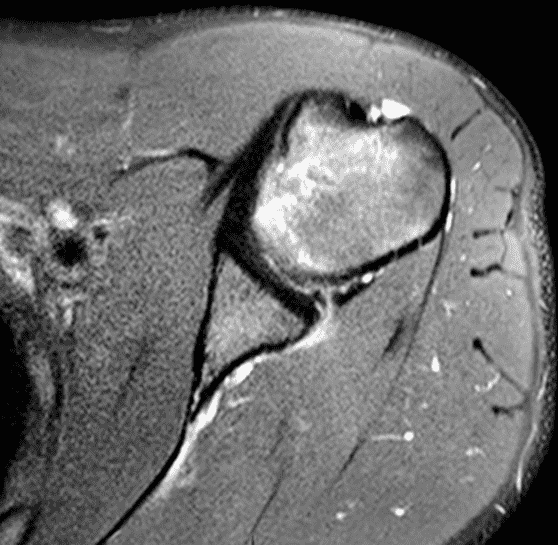

20 year old right-handed hitting college baseball player with left shoulder injury. Fat-suppressed proton-density-weighted axial images at the mid (1A) and inferior (1B) left glenohumeral joint are provided. What are the findings? What is your diagnosis?

Figure 2: The axial images (2A and 2B) demonstrate findings of a posterior glenohumeral instability injury including posterior to posteroinferior capsulolabral tearing and pericapsular edema (solid arrows) and an anteromedial humeral head impaction injury (dashed arrows).